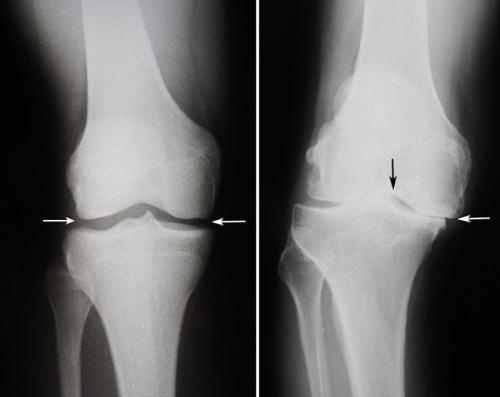

Коленный сустав. Какие бывают болезни коленного сустава: список самых распространенных

частые патологии опорно-двигательного аппарата. Около 15% пациентов ортопедо-травматологических стационаров попадают туда именно из-за проблем с коленями. Давайте посмотрим, какие бывают болезни коленного сустава.

В зависимости от причин возникновения все болезни коленных суставов можно разделить на несколько больших групп. Для каждой из них характерны свой механизм развития и симптоматика.

Виды заболеваний коленных суставов:

- воспалительные. Характеризуются развитием инфекционного или асептического воспаления различных структур коленного сустава. Могут возникать в любом возрасте. Причины патологиизанесение инфекции в сустав или наличие воспалительного процесса в организме.может быть как острым, так и хроническим. Воспалительные процессы также могут развиваться на фоне длительного течения;

- дегенеративно-дистрофические. Чаще встречаются у пожилых людей и лиц, которые постоянно выполняют тяжелую физическую работу. Дегенеративные процессыэто следствие старения организма, которое сопровождается замедлением метаболизма и кровообращения в суставах. Под действием провоцирующих факторов (физические нагрузки, нехватка кальция, обменные нарушения) суставные хрящи начинают разрушаться, что приводит к развитию патологии. Дегенеративно-дистрофические заболевания имеют хроническое, медленно прогрессирующее течение;